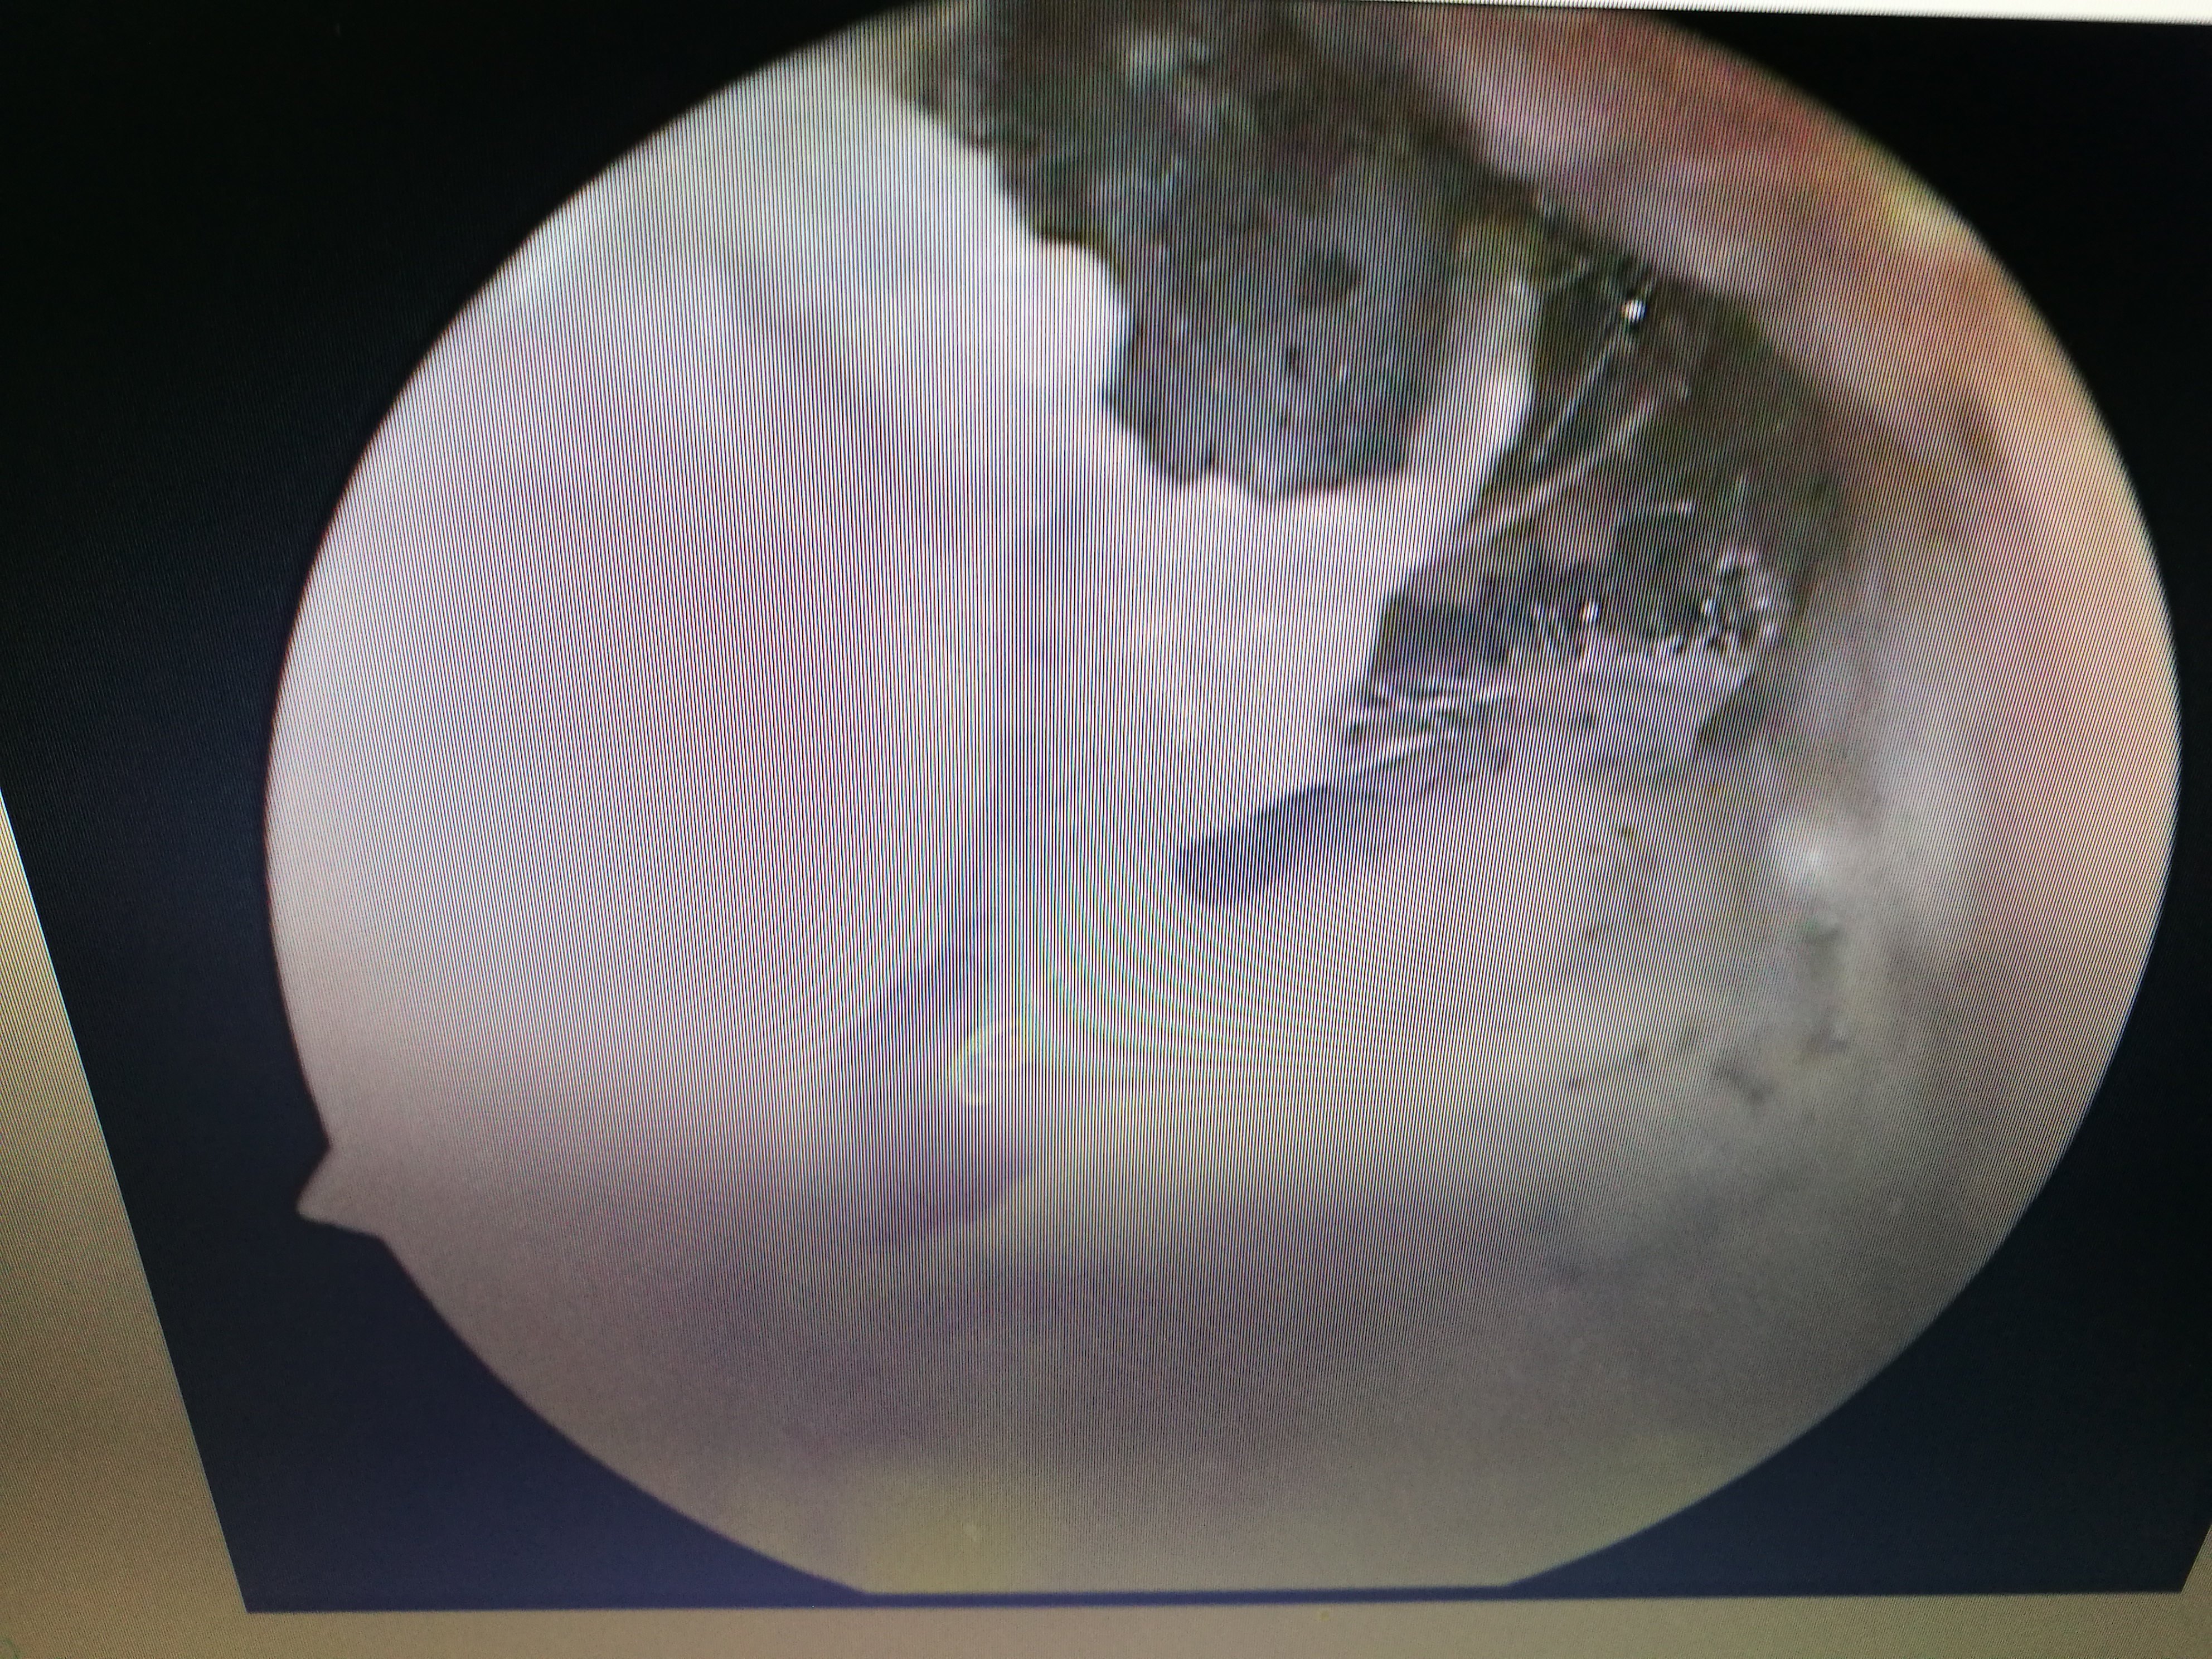

External auditory canal fungus infection, moldy ear wax blocks the ear completely耳朵也会"发霉" "我的耳朵痒死了! 整晚都没睡好,快帮我治治吧! " 通过鼻内镜检查,发现患者外耳道内都是霉菌样物,被诊断为外耳道真菌病。 外耳道真菌病是外耳道皮肤的亚急性或慢性炎性疾病,多数认为是由真菌感染所致,常合并细菌感染。 此病好发于高温、潮湿的季节,且常见于热带或亚热带地区,如我国长江及珠江流域。 引发外耳道真菌病的病菌耳朵一直响个不停听力下降怎么办 问答 网: 听力下降,不应该因为生气而引起的,还是要注意一下器质性的原因,你最好是做一下电测听 耳朵响个不停,听力也下降了,到底该怎么办?

「医生,我的耳朵好痒,感觉和人讲话隔了一层膜,听话也听不太清了!整晚都没睡好,您快帮我看看吧!」7 月 8 日,30 岁的小田(化名)到宜昌市第一人民医院耳鼻喉科就诊,经耳内镜检查发现,他的右侧耳道充 中国宁波网记者 陈敏 通讯员 陆达锴 郭豪伦 长期掏耳朵,竟导致耳道内长满了霉花,甚至影响了听力。说起自己的这个怪病,家住海曙区的张先生男子采耳后患上"脚气病"?医生透露原因 采耳后,耳朵为何会患上"脚气病"? 主治医师高险亭表示,这些患者基本都是因为耳朵痒、耳朵不舒服来就诊,检查结果显示耳朵已经发霉,满是霉菌,患上真菌

医生告诉记者,在洗头店、洗浴中心等处的非专业采耳,是真菌性外耳道炎感染途径之一,如果挖耳勺没有清洁干净,在掏耳朵的时候又不小心弄伤了脆弱的外耳道皮肤,就很容易引起病菌感染。 "而且平时在洗浴之后耳道进水,潮湿的耳道也给真菌提供了绝佳的生长温床,进而感染上了真菌性外耳道炎。 "医生说。 另外,朱先生在平时耳朵或其他身体不适时习惯性 医生说,这是耳朵里面发霉了!原来这是一种典型的外耳道疾病:霉菌性外耳道炎,又叫外耳道真菌病,它是一种外耳道的真菌感染性疾病,临床并不少见。 霉菌性外耳道炎是由霉菌感染所引起的,属于机会感染。 致病原因主要有 1、机体免疫缺陷或抵抗力下降;